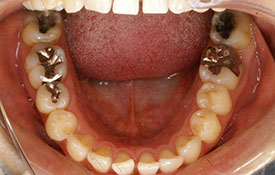

叢生|ブラケットを用いた治療

CASE 1

CASE 2